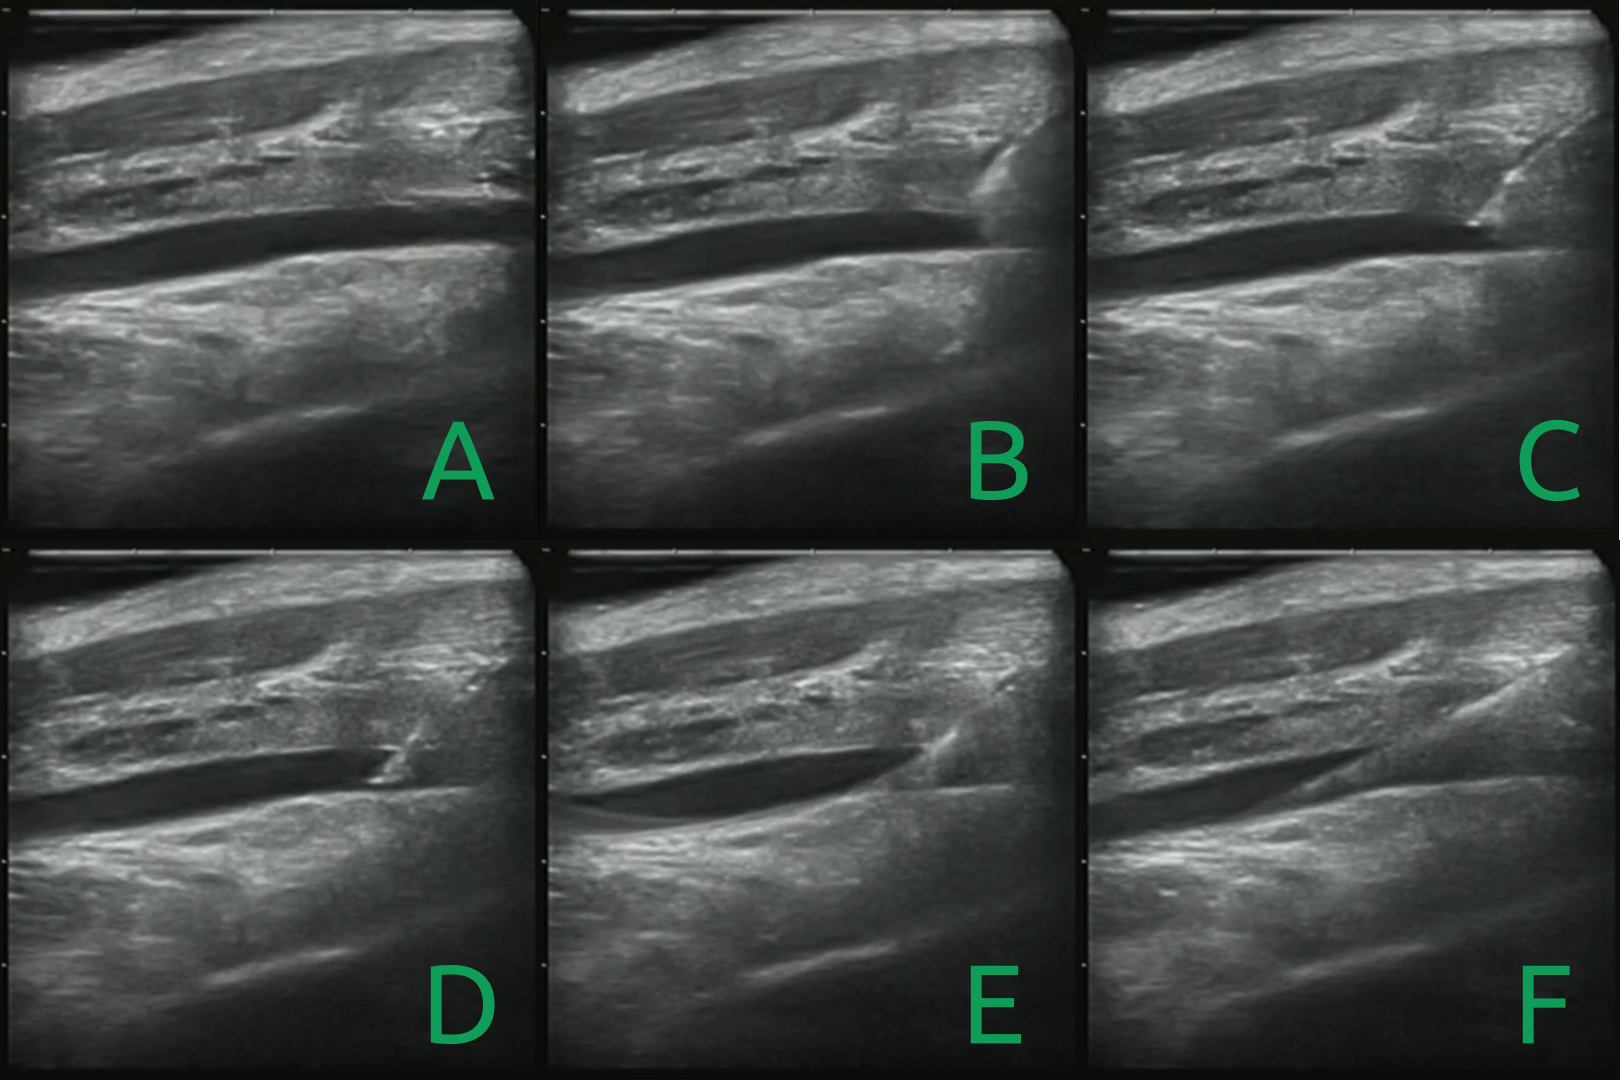

IV-A Ultrasound scanning (1-3)

One of the core components of the system was the ability to perform smooth, even scans of the femoral region. Constant pressure was important to maintain good ultrasonic coupling necessary for imaging. These scans, though not strictly necessary for insertion, help the operator get a situational awareness of the underlying anatomy. This scanning data will also help in the future as we train automatic vessel detection algorithms.

To begin a scan, a trajectory of scanning locations were manually chosen on the surface of the surface based on the choice of the artifact to be captured using ultrasounic imaging. Then starting from a safe position a hybrid force-position controller was used for scanning the surface. The force controller ensured a constant contact of the ultrasound probe with the patient’s skin surface. A position controller drove the ultrasound controller from the initial point to the final point of scan while moving compliantly in the vertical axis of the ultrasonic probe. The controller is explained in more detail in [7].

Our approach relied heavily on an augmented ultrasound image (Fig. 4). After a simple calibration which allowed us to convert ultrasound image space into real-world distance, a click on the image frame commanded the robot to move the ultrasound probe so that point was now located in the center of the frame. We also added additional buttons to control the rotation and non-planar position of the robot. This intuitive motion model made it possible for a user to simultaneously center the vessel in the center of the image and rotate until the vessel is transverse to the ultrasound probe (4).

V-B In-vivo results

This system presented in this paper was also used in three in-vivo porcine surgeries. In each experiment, an operator followed the procedure described in section IV. In addition, once the guidewire was placed, a catheter was slid over the guidewire and the guidewire was removed by the operator, completing the full procedure for femoral access.

These experiments differed from those performed on the phantom in several ways. First, the vasculature was much more prone to rolling, and deforming under the needle than in the phantom. In addition, the non-uniformity of the tissue could cause the needle to bend or deflect slightly. Finally, the geometry of the femoral triangle is much more curved near the femoral triangle in pigs than it is in humans.

Despite these challenges, the operator was able to use the system cannulate the femoral artery, place a guidewire, and use that guidewire to place a catheter in each of the three pigs, without causing complications such as lacerations or hematomas. While this may not be a particularly impressive feat for a trained surgeon, we consider it a great success considering the operators had no formal medical training. Though more experimentation must be undertaken to fully assess the efficacy and usability of the system, these experiments show the system’s real world operablility, and is a significant step in our goal of fully automating this procedure.

In this paper we present a system capable of teleoperated needle insertion. This needle insertion allowed for subsequent guide wire and catheter insertion. The main contributions of this paper are the development of a robotic system capable of assisting a human with this medical procedure in a way that is reliable enough to test in-vivo. By understanding how a human will interact with this device we can now continue to collect data at each state of the insertion process and ultimately decide to either further assist or phase out the human operator. Moving forward, our biggest challenges will likely be in the realm of sensing and computer vision; generating enough labeled sub-dermal images and needle insertion data for the development of models capable of understanding ultrasound, puncture forces, and the dynamic environment of subdermal anatomy. Currently, the most time consuming part of the procedure is aligning the robot with the artery in the longitudinal plane, especially on pigs where the vasculature is more curved than on humans. In order to automate this process, we will need to reconstruct a 3D model of the vessels and surface of the skin. In addition, while a flush of blood indicating a successful cannulation is guaranteed in the femoral artery of a healthy patient, patients with low blood pressure such as those in trauma will require more sensitive methods to detect puncture such as force, bio-impedance, or pressure sensors.